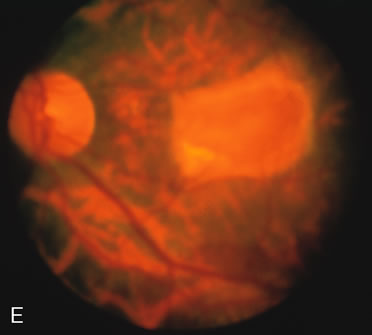

HEREDITARY HEMORRHAGIC MACULAR DYSTROPHY (PSEUDOINFLAMMATORY MACULAR DYSTROPHY OF SORSBY)

FA plays an important role in the understanding of this rare disorder. In the earliest manifestations of the disease, FA shows a single, isolated choroidal neovascular membrane unassociated with other causes of a membrane, such as drusen or angioid streaks (Fig. 13).25 Presumably this membrane is the cause of the subsequent hemorrhagic maculopathy with secondary disciform scarring, occurring initially in the macula but often extending throughout the retina.

Fig. 13. Hereditary hemorrhagic macular dystrophy (pseudoinflammatory macular dystrophy of Sorsby). Fluorescein angiography in this family member demonstrates that the earliest finding is an isolated choroidal neovascular membrane B). Despite laser photocoagulation, a hemorrhagic maculopathy developed in this eye (C, D) and eventually a disciform scar (E) formed, as it had in the fellow eye, and in the eyes of other affected family members.

Abnormal choroidal perfusion, manifested on FA as a delay in choriocapillaris filling, has been seen in the restudy of some of Sorsby's initial pedigrees.26 This unusual pattern has been related to the histopathologic finding of a “confluent, lipid-containing, amorphous deposit found between the basement membrane of the RPE and the inner collagenous layer of Bruch's membrane.”27